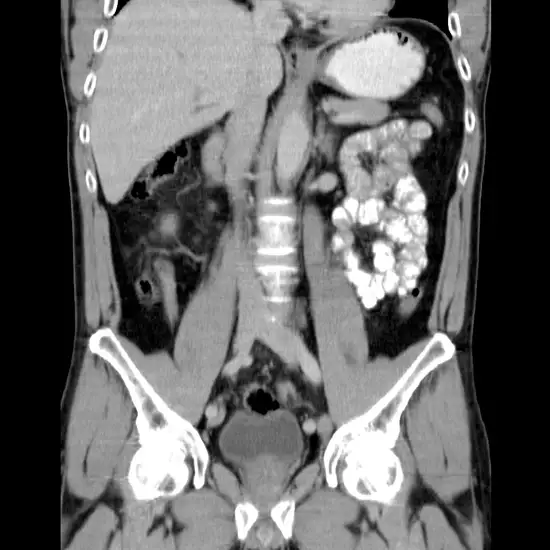

CT 3D Both Hip Joints (Three-Dimensional Computed Tomography for Both Hip Joints) is an imaging scan that is used to produce the three dimension (3D) images of both hip joints. As compared to regular CT scan for both hip joint, CT 3D for both hip joints obtains more detailed images and make it easy for a doctor to identify the problems in the hip area.

A 3D CT Both Hip Joint scan is useful as a diagnostic technique. It is basically an imaging scan, that is used to visualize the internal structures of the Both Hip Joint without an incision in a 3D reconstruction model.